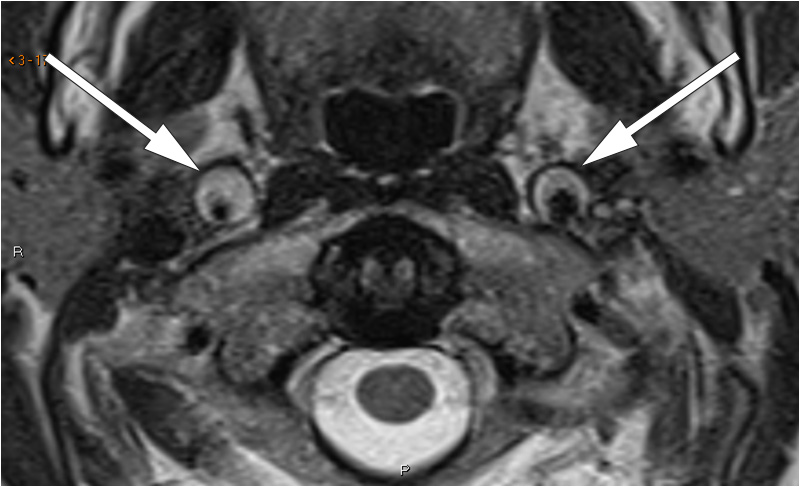

Nevrologisk undersøkelse avdekket Horners syndrom. CT-angiografi viste fortykket karvegg i begge a. carotis interna, mest uttalt på høyre side, fra like over bifurkaturen til skallebasis. MR-angiografi og T2-vektede bilder bekreftet bilateral carotisdisseksjon, med minste lumendiameter 2 mm på høyre side (bildet til venstre og bildet i midten). Fettsupprimerte T1-vektede bilder (bildet til høyre) viste høyt signal i arterieveggene, forenlig med intramurale hematomer.